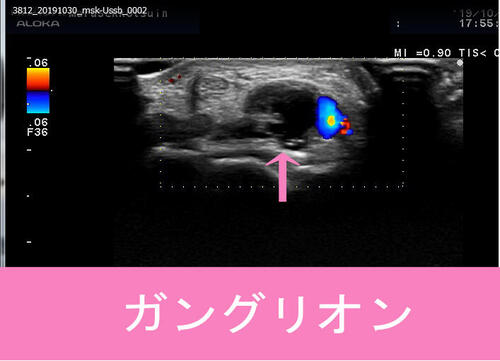

今回の患者さまも、エコーで確認すると、橈骨動脈という手首の血管のすぐ脇にできており、

今後、大きくなると疼痛や蒼白感などの異常をきたす疑いがあったので、

提携整形外科にて穿刺をして吸引排出して頂きます。